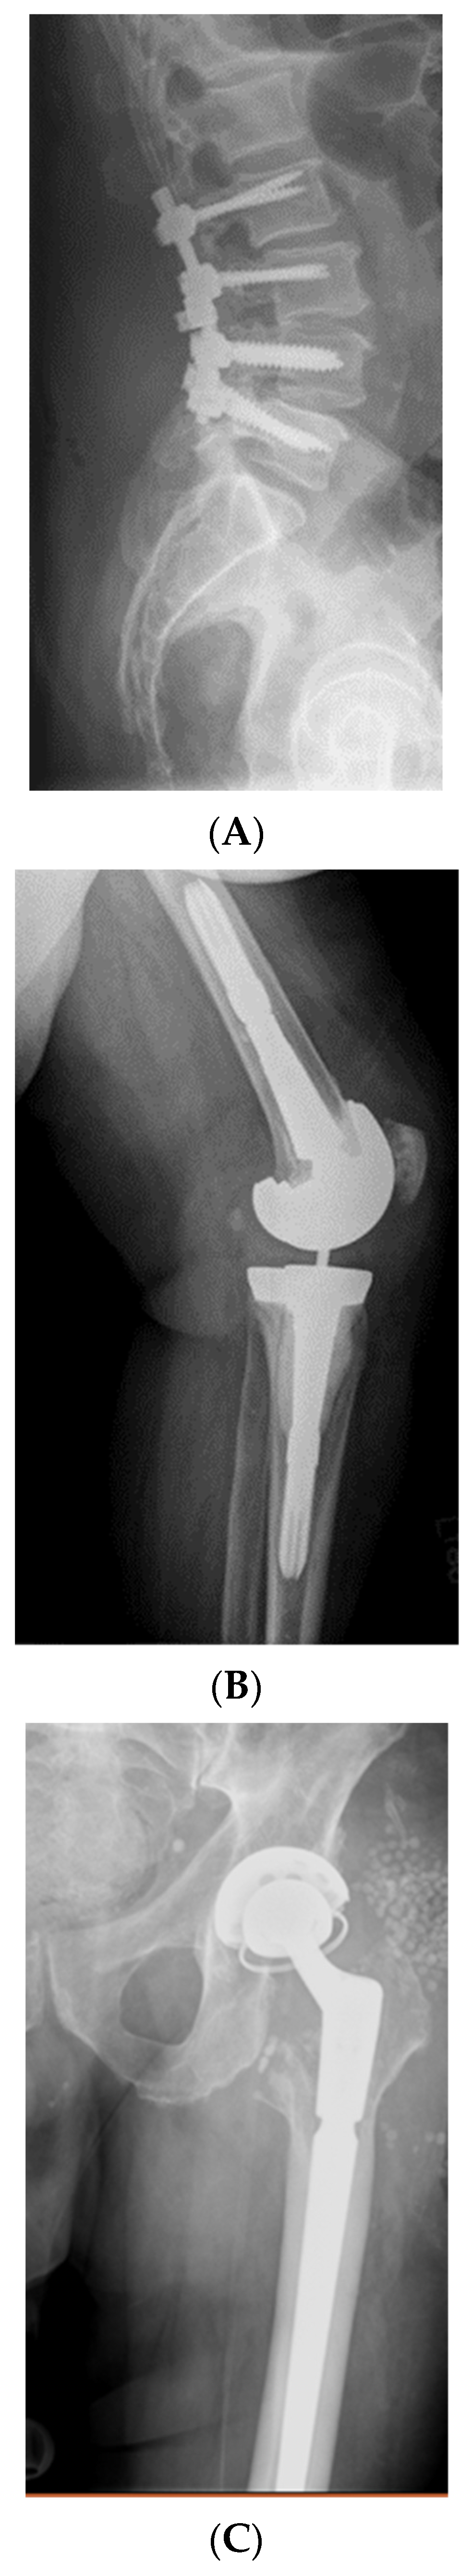

3.1. Case Studies of Intravenous Bacteriophage Therapy in Biofilm Infections

3.2. Case Studies of Direct Injection of Bacteriophages to Biofilms with Surgical Intervention